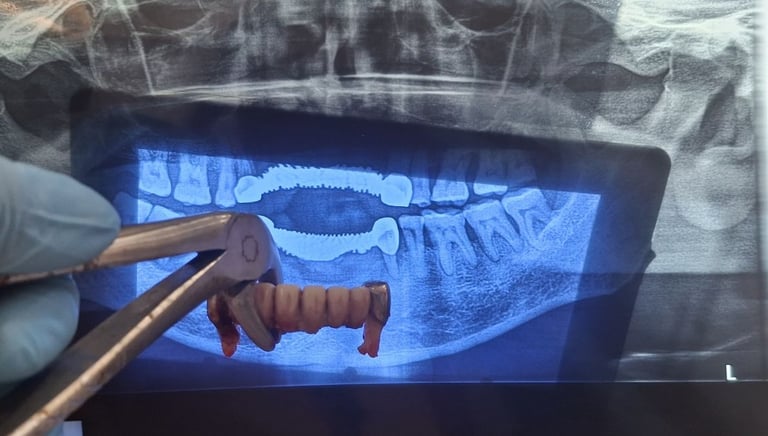

Teeth Extraction

All images shown here represent real clinical cases of teeth extractions done at our dental clinic with patient consent.

Tooth extraction is performed when a tooth is severely damaged, infected, or cannot be saved through other dental treatments. At Shree Dental Care, we carry out tooth extractions using gentle techniques to ensure minimal discomfort and faster healing.

Patients from Shyamal and nearby areas of Ahmedabad visit our clinic for comfortable teeth extractions carried out using modern techniques and strict hygiene protocols.

At Shree Dental Care, we ensure:

Thorough clinical examination and digital X-rays.

Gentle and painless extraction techniques.

Proper anesthesia for patient comfort.

Post-extraction care instructions for fast healing.

Our goal is to make the procedure as smooth and stress-free as possible.